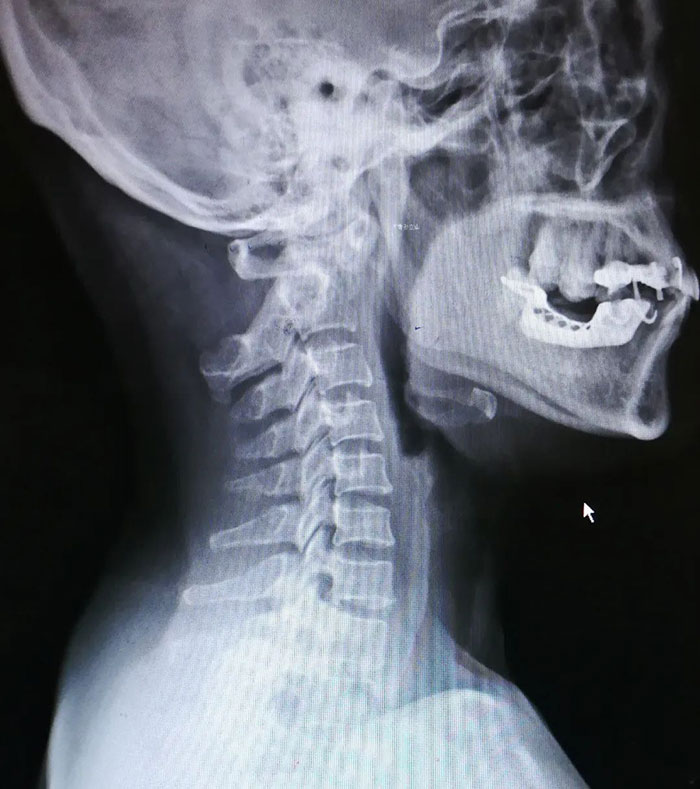

入院檢查顯示患者齒狀突骨不連,寰樞椎脫位

王麗國(guó)主任憑借專業(yè)敏銳性,豐富的臨床經(jīng)驗(yàn),馬上就判斷出是上頸椎不穩(wěn)導(dǎo)致的脊髓受壓。后經(jīng)頸椎磁共振和CT檢查后,發(fā)現(xiàn)劉女士有齒狀突骨不連,寰樞椎不穩(wěn),低頭時(shí)寰椎前移,壓迫脊髓,引發(fā)四肢麻木,憋氣,如再不及時(shí)進(jìn)行手術(shù),病情會(huì)快速加重,甚至?xí)斐砂c瘓。脊柱外二科(骨二科)團(tuán)隊(duì)結(jié)合劉女士實(shí)際情況制定了科學(xué)周密的治療方案。